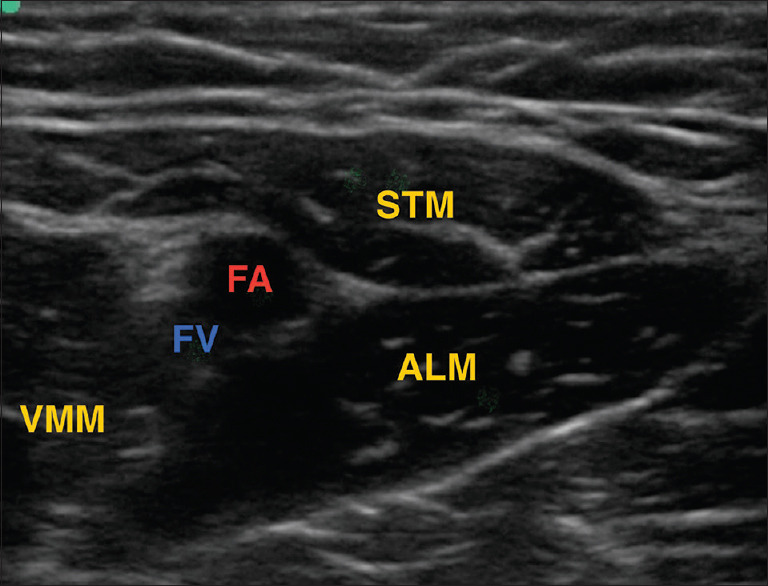

Material and methods: Sixty patients aged 18-80 years and ASA grade I-III undergoing unilateral TKA were randomised to two groups postoperatively to receive DSB or SSB. Patients in group DSB received distal femoral triangle block (15 ml) + proximal adductor canal block (20 ml), while group SSB received only proximal adductor canal block (20 ml). Primarily, the changes in pain intensity and pain control in terms of static and dynamic visual analogue score (VAS) with the duration of analgesia and cumulative dose requirement of rescue analgesic in the first 24 hours postoperatively were studied. Secondary outcomes were the postoperative degree of motor blockade, the ability of early ambulation, patient satisfaction and complications. Statistical analysis was done using the student t-test and Chi-square test using MedCalc version 12.4.3.0.